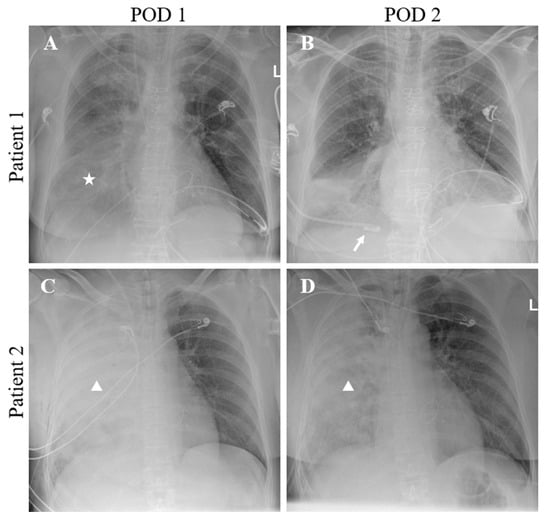

Redefining Unilateral Pulmonary Edema after Mitral Valve Surgery on Chest X-ray Imaging Using the RALE Scoring System

2.2. Chest X-ray Analysis and Diagnosis of UPE

3.2. Chest X-ray Analysis and Diagnosis of UPE